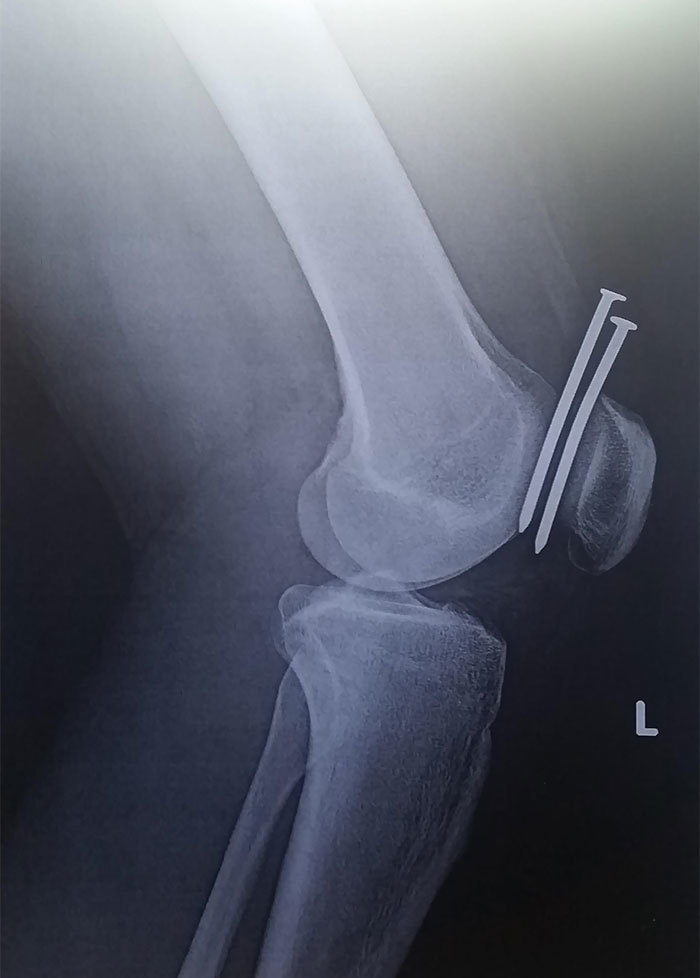

文章插图

这个家伙用钉子枪打了两个钉子砸了他的腿 , 他们都错过了他的股骨和膝盖骨